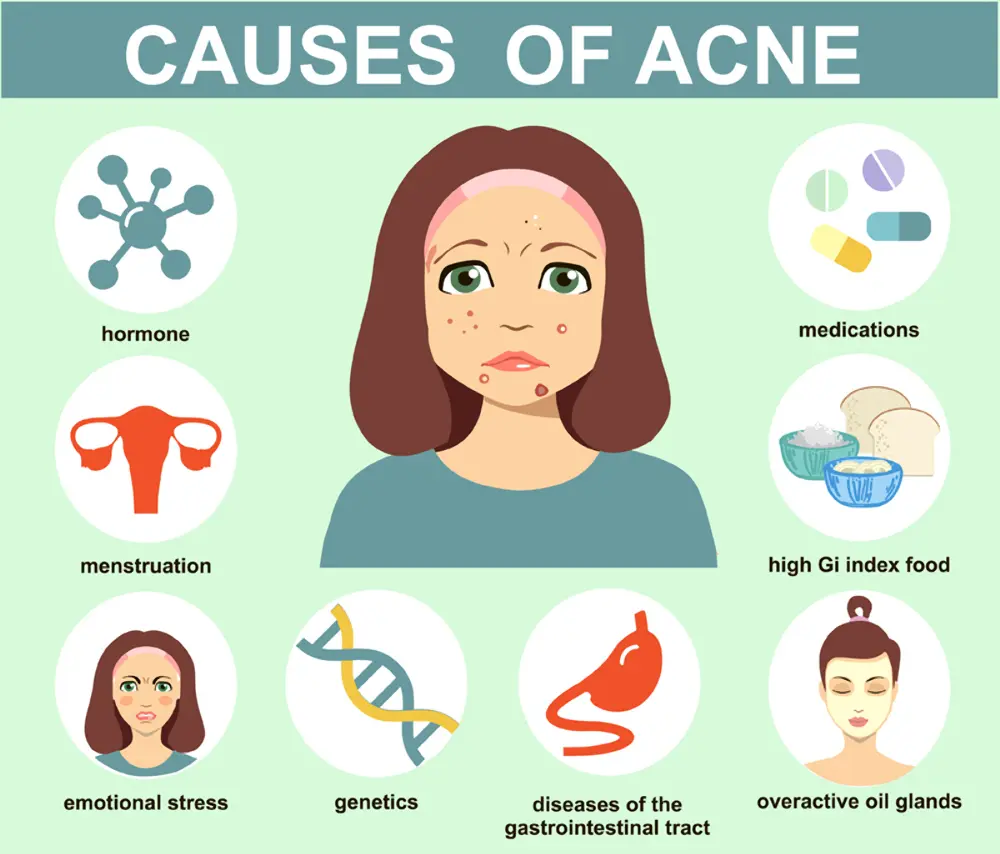

Causes of Acne

Acne is caused by a combination of factors, including overactive sebaceous glands, bacteria, and the buildup of dead skin cells.

Hormones

Genetics

Genetics can play a big role in development of Acne conditions. Acne may run in families, and some people are more likely to develop acne than others based on their genes. Some of the genes that have been linked to acne include those that control oil production, inflammation, and sebum production.

Poor Diet

There is a link between a poor diet and Acne. In fact, a diet high in processed foods and sugar can actually worsen acne. This is because sugary foods promote the overproduction of sebum, which is the oil that helps to breakout your skin. Additionally, diets high in unhealthy fats can also lead to an increase in sebum production. Poor diet can lead to an imbalance of the hormones that control oil production and inflammation, which can trigger acne. Some of the foods that are most commonly linked to acne include processed foods, sugary drinks, and junk food. It’s important to make sure that you’re getting all of the nutrients your body needs to fight acne and keep your skin looking healthy.

Stress

When you’re under a lot of stress, your body starts producing more cortisol, which can cause acne. Cortisol is a hormone that’s responsible for regulating your blood sugar and helping you to fight off infection. It can also play a role in the production of oil and sweat, which can lead to acne. If you have acne and you’re stressed out, there are some things that you can do to reduce your stress levels and improve your acne. First, try to get enough sleep.